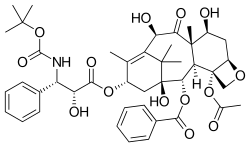

Chemistry

Docetaxel is of the chemotherapy drug class; taxane, and is a semi-synthetic analogue of paclitaxel (Taxol), an extract from the bark of the rare Pacific yew tree, Taxus brevifolia.[13] Due to scarcity of paclitaxel, extensive research was carried out leading to the formulation of docetaxel – an esterified product of 10-deacetyl baccatin III, which is extracted from the renewable and more readily available leaves of the European yew tree.

Docetaxel differs from paclitaxel at two positions in its chemical structure. It has a hydroxyl functional group on carbon 10, whereas paclitaxel has an acetate ester, and a tert-butyl carbamate ester exists on the phenylpropionate side chain instead of the benzamide in paclitaxel. The carbon 10 functional group change causes docetaxel to be more water-soluble than paclitaxel.[13]